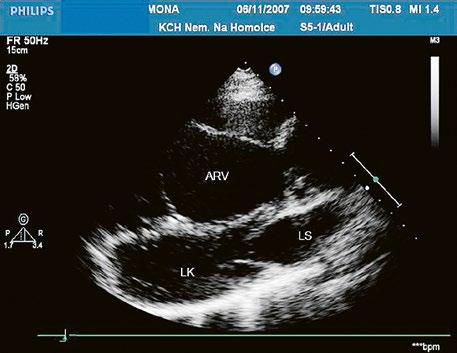

Obr. 45.24 TTE, parasternální dlouhá osa, těsně pod aortální chlopní (AO) je patrná diskontinuita v oblasti membranózního septa (šipka) s levopravým zkratem mezi levou komorou a pravou komorou LK – levá komora, LS – levá síň, PK – pravá komora

Video 45.22 TTE, parasternální dlouhá osa, barevný levopravý zkrat perimembranózním defektem komorového septa z levé komory do pravé komory